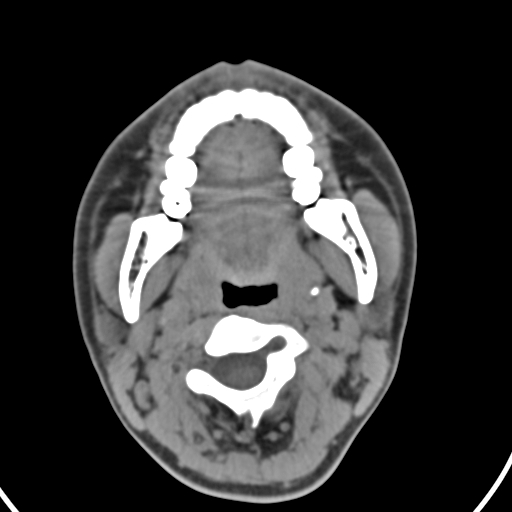

以下是引用zjzjr在2008-12-5 11:46:00的发言:[br]脂肪密度,壁有钙化.考虑口咽部皮样囊肿可能性大.双侧上颌窦炎,双侧下鼻甲粘膜肥厚.增殖腺肥大,扁桃体亦增大,考虑炎性.

以下是引用随光逐影在2008-12-5 18:27:00的发言:[br]1)考虑左侧茎突过长综合征并茎突舌骨韧带囊肿形成突入咽部;左侧咽部慢性炎症。2)鼻咽腺样体肥大。3)双侧扁桃体肿大。4)双侧上颌窦炎。5)双侧下鼻甲粘膜肥厚。